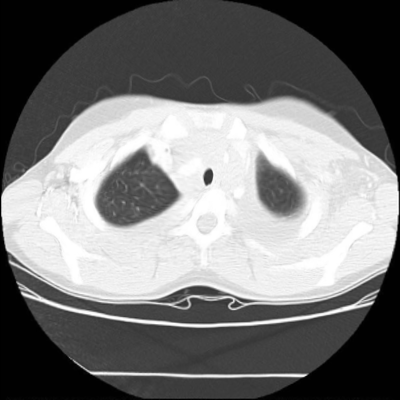

We now consider applying the proposed image registration method on real lung CT images retrieved from the National Lung Screening Trial (NLST) dataset [1]. Fig. 9(a) and Fig. 9(b) show two slices of lung CT images that we use as the source and the target (see Fig. 9(c) for the absolute intensity difference). We remark that the CT images are originally with different intensity, and so we apply an intensity histogram matching before running the registration experiment. Fig. 9(d) shows the registration result obtained by our proposed method. It can be observed that our method successfully produces a large deformation on the right lung of the source image to match that of the target image (see also Fig. 9(e) for the final absolute intensity difference). On the contrary, DDemons [47] (Fig. 9(f)), LDDMM [5] (Fig. 9(g)), Elastix [29] (Fig. 9(h)) and DROP [18] (Fig. 9(i)) all fail to produce an accurate and bijective registration result. This shows that our method is more capable of handling large deformation image registration.

We then test our method on slices of chest CT images obtained from the Open Access Biomedical Image Search Engine [2]. Fig. 10(a) and 10(b) show the source image and target image respectively, and the intensity difference is shown in Fig. 10(c). The registration result obtained by our proposed method is shown in Fig. 10(d) (see also the result with the deformed underlying grid in Fig. 10(e)). From the final intensity difference plot in Fig. 10(f), it is easily to see that our method matches not only the two large components but also the small dot at the center very well. On the contrary, DDemons [47] produces a suboptimal registration result with a significantly larger mismatch of the small component at the center (see Fig. 10(g) and Fig. 10(h)).